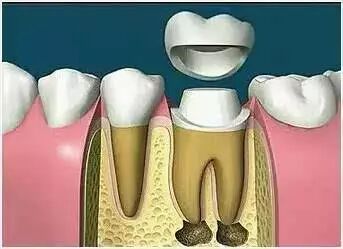

六、根管治疗后为什么还需要做全冠保护?

很多病人不理解,为什么在根管治疗后,牙齿不疼了,补上就可以了,为什么还要做全冠保护,觉得没有必要。

事实上在根管治疗后,没有牙髓提供营养的牙齿会变暗、变脆,剩余的牙冠部分很容易折断劈裂,导致牙齿使用寿命减少,因此根管治疗后需做全冠对其进行保护。